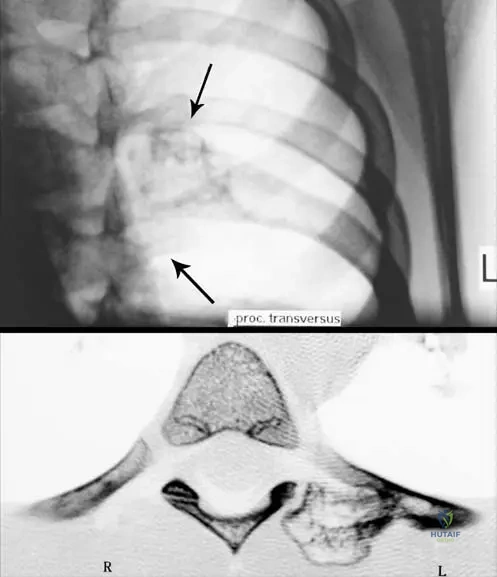

A 16-year-old male presents with pain and swelling in his mid-tibial diaphysis. Radiographs show a partially mineralized mass on the surface of the bone with ill-defined margins. The mass appears denser near the cortex, with an unmineralized soft tissue component superficially. There is no apparent involvement of the underlying medullary canal in the early stages.

View Answer & Explanation

Correct Answer: C

Rationale: Periosteal osteosarcomas are grade 2 surface tumors usually affecting the diaphysis of long bones. They present with a partially mineralized mass on the surface of the bone with ill-defined margins, denser near the cortex, and an unmineralized soft tissue component on the surface. Crucially, there is no involvement of underlying marrow in the early stage. This description matches the vignette and the provided image (Fig. 8.70 a, b) of a periosteal osteosarcoma of the tibial diaphysis. Parosteal osteosarcoma is heavily mineralized and metaphyseal. Conventional osteosarcoma is intramedullary. High-grade surface osteosarcoma is also surface but often more circumferential and heavily mineralized, with significant cortical reaction. Ewing sarcoma is typically lytic with an onion-skin periosteal reaction and small round blue cells on histology.